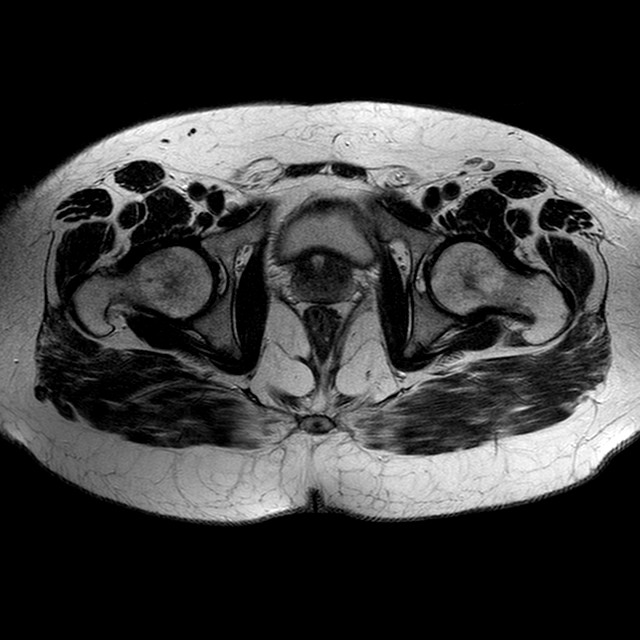

Esami: RMN BACINO

T2w TSE

Evidenti e simmetriche alterazioni osteofitosiche in regione coxo femorale con riduzione delle rime articolari. Degenerazione completa del cercine glenoideo. Non attuali segni di versamento articolare. Non segni di edema osseo che escludono attuale algodistrofia od osteonecrosi. Lieve e simmetrica riduzione del trofismo della muscolatura glutea.